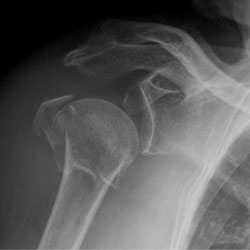

مفصل شانه شامل مفصل گلنوهومرال وآکرومیو کلاویکولار است. مفصل گلنوهومرال استخوان بازو و کاسه گلوئید استخوان شانه را به یکدیگر متصل میکند. مفصل آکرومیوکلاویکولار اتصالی بین استخوان آکرومیون شانه و ترقوه است. شکستگی مفصل شانه شامل شکستگی بخش پروگزیمال (نزدیک به مفصل شانه) باستخوان بازو، حفره گلنویید، آکرومیون، زائدهٔ کوراکویید، ناحیه گردن شانه، بدنه شانه و استخوان ترقوه است. مفصل گلنو هومرال مفصل گوی و کاسهای سینوویال است. اکثر حرکات مفصل شانه در مفصل گلنوهومرال رخ میدهند. شکستگی انتهای جانبی (مفصل بیرونی در نزدیکی شانه) ترقوه شایعترین نوع شکستگی مفصل شانه در کودکان است. شکستگی انتهای فوقانی (پروگزیمال) استخوان بازو، شکستگی معمول در بیماران بزرگسال است. شکستگی حفره گلنوئید همراه با جابجایی یا در بیماران مسنتر دیده میشود.

بررسی و آزمایشهای تشخیصی برای شکستگی مفصل شانه

یک پزشک پس از معاینه کامل فیزیکی و تصویربرداری قادر خواهد بود تیغهٔ شانهٔ شکسته را تشخیص دهد.

- از شانه و قفسه سینه با استفاده از اشعه ایکس تصویربرداری میشود.

- سی تی اسکن شکم و قفسه سینه گاهی اوقات برای ارزیابی آسیبهای دیگر انجام میشود.

- گاهی لازم است که سی تی اسکن شانه برای تشخیص شکستگی کاسهٔ شانه (گلنوئید) انجام شود.